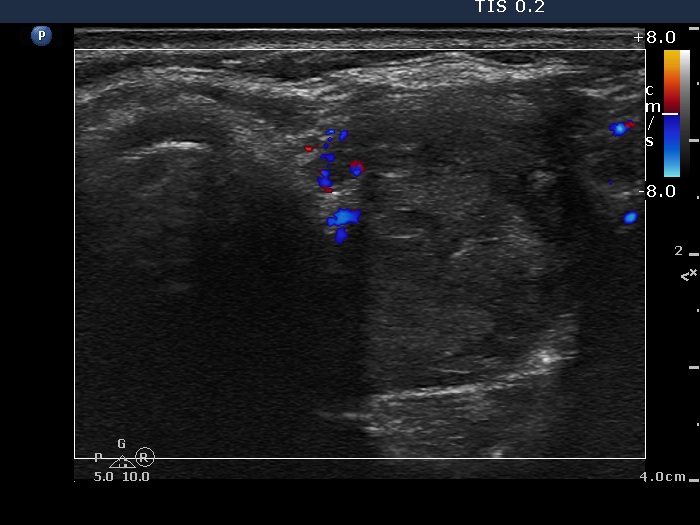

Follow-up investigation 6 months after first visit (ultrasonographic picture 8)

Upper part of the left lobe, transverse scan, color Doppler mode.